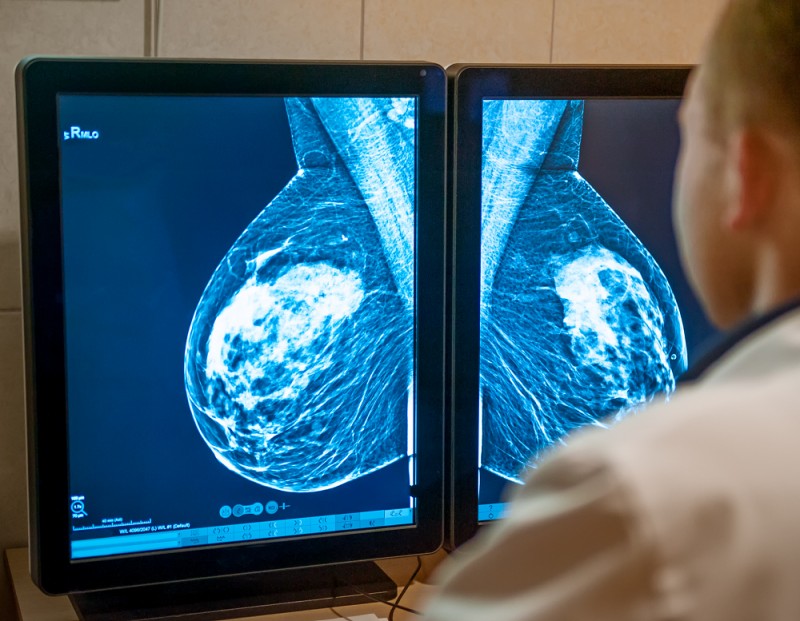

A Agência Nacional de Saúde Suplementar (ANS) desmentiu nesta quinta-feira (9), em Belo Horizonte, as informações de que seria contrária à realização de mamografia por mulheres com menos de 50 anos. Assessora do órgão, Kátia Cursi destacou que o que houve foi um equívoco sobre a compreensão da Consulta Pública 144, disponibilizada pela agência.

“O objetivo da consulta foi instituir o Programa de Certificação de Boas Práticas em Atenção à Saúde das Operadoras de Planos Privados de Assistência à Saúde. Nesse ponto, ela recomendava a busca ativa das pacientes entre 50 e 69 anos que não haviam realizado o exame, mas de forma alguma restringia a realização a partir dos 40 anos. Inclusive, para mulheres com fatores de alto risco, esse rastreamento pode acontecer antes disso”, destacou.

“Dados de 2022 mostram que o câncer de mama foi responsável por 13 óbitos em cada 100 mil mulheres. O diagnóstico tardio é o grande problema, por isso os exames preventivos devem começar cada vez mais cedo."

Pesquisas demonstram que até 23% das mortes causadas pela doença entre mulheres de 40 a 50 anos poderiam ser evitadas com a realização da mamografia preventiva, o que traria um impacto financeiro de R$ 100 milhões anuais para o Estado.Para ampliar os cuidados, Minas garantiu 64 novos mamógrafos que vão operar em diferentes regionais do Estado, segundo Fernanda Vilarino Jorge, representante da Secretaria de Estado de Saúde.